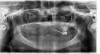

len4a Опубликовано 23 января, 2013 Поделиться Опубликовано 23 января, 2013 Имеется 2 почти полных съёмника и 1 оставшийся зуб. Сделала ОПТГ. Чтобы не шокировать лаборантку беззубыми челюстями, и чтоб лучше зафиксировать их в одном положении, решила сделать снимок "в зубах". Дома посмотрела результат и испугалась, толи у меня кости СОВСЕМ нет, толи съёмники и Корега в 3 слоя фонят? Посмотрите пожалуйста, нужно переделывать снимок, или всё видно? Собственно интересует низ. Два года назад всё удалили, планировалась имплантация, и верх, и низ. Но финансовые обстоятельства изменились, и осталась я в итоге с двумя съёмниками, которые держатся только на Кореге, ито кое-как. Удовольствие, конечно, ниже среднего.)Какие возможности у меня остались? Сколько максимально, или оптимально, имплантов можно установить вниз? Можно ещё мечтать о подсадке блоков в боковые отделы, или про это уже забыть и думать только о балке? Ссылка на комментарий

Bier Опубликовано 23 января, 2013 Поделиться Опубликовано 23 января, 2013 надо на толщину гребня смотреть, по высоте ситуация более-менее удобоваримая. Во фронтальном отделе так вообще нормально.на 4х имплантатах можно сделать хороший съемный протез на балочной фиксациивот наверху совсем беда у вас. 2 Ссылка на комментарий

Mane Опубликовано 23 января, 2013 Поделиться Опубликовано 23 января, 2013 низ - если идти от простого - то это 4 импланта и съемник на балке, если интреснее - то блоки - потом 8 имплантов - потом несъемная конструкцияверх - синус лифтинг с двух сторон, потом импланты 4 шт - потом съемник на балке. Вам на верху грозит только съемник ввиду значительной убыли костной ткани. Ссылка на комментарий